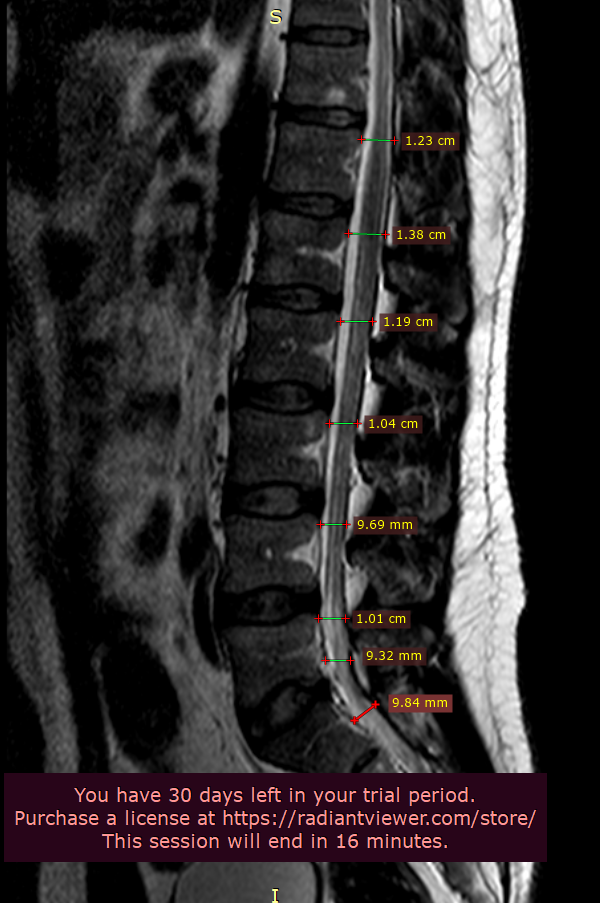

ПОП.

Получено изображение сегментов Th12-S4. Дистрофические изменения 1 стадии во всех исследованных сегментах, в виде полосовидной дегидратации м/п дисков. Изменений дугоотростчатых суставов не выявлено. Физиологический лордоз сглажен, сколиотической деформации позвоночника не определяется.

Мелкая гемангиома тела Th11 – 6 мм.

Диффузное выбухание диска и мелкая протрузия на широком основании в сегменте L4-L5, сагиттальным размером 2-3 мм, с лёгким дискодуральным конфликтом, лёгким сужением радикулярных карманов и межпозвонковых отверстий.

Мелкая центральная протрузия в сегменте L5-S1 с лёгким дискодуральным конфликтом. Паравертебральные мягкие ткани не изменены. Данных за t-r spinalis

Новообразований не определяется. Каудальные сегменты спинного мозга и корешки конского хвоста не изменены. Патологического отека тел позвонков не определяется.

Исходный сагиттальный размер позвоночного канала на уровне L3-S1 не более 14 мм.

Заключение:

Остеохондроз L1-S1 - 1 стадии. Врожденный, относительно узкий позвоночный канал. Диффузное выбухание диска и мелкая протрузия на широком основании в сегменте L4-L5. Мелкая центральная протрузия в сегменте L5-S1. Рекомендована консультация невролога.